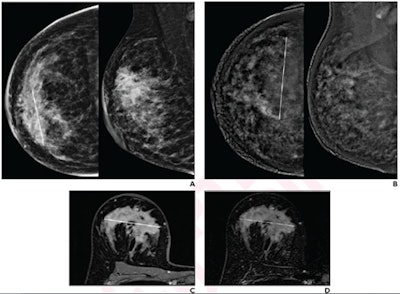

(A) Low-energy images from contrast-enhanced mammography (CEM) before neoadjuvant show a 60-mm architectural distortion in the central portion of the right breast. (B) Recombined images from pre-therapy CEM show marked background parenchymal enhancement; 90-mm non-mass regional enhancement (line) was described. (C) Axial fat-saturated T1-weighted unenhanced MR image shows a 70-mm hypointense irregular mass (line) with not circumscribed margins in the central portion of the right breast. (D) Axial fat-saturated T1-weighted post-contrast MR images show corresponding fast initial enhancement (line) with delayed plateau. All images are from a 41-year-old woman with invasive DCIS of the right breast. Images courtesy of the American Roentgen Ray Society and the American Journal of Roentgenology.The team found that CEM showed lower average lesion size than MRI in pre-therapy by 0.2 mm, by 0.7 mm during therapy, and by 0.3 mm post-therapy. All post-therapy imaging tests showed systematically larger lesion size versus pathology, including by 0.8 mm for CEM, 1.2 mm for MRI, and 1.9 mm for delayed CEM.